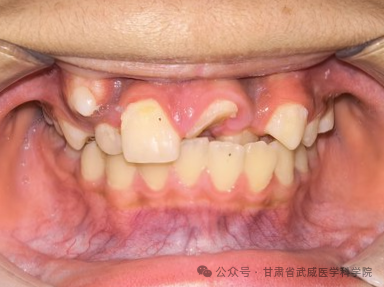

牙列不齐,医学上称为“错颌畸形”,是指儿童在生长发育过程中,由先天的遗传因素或后天的环境因素(如疾病、口腔不良习惯、替牙异常等)导致的牙齿、颌骨、颅面的畸形。

·清洁死角多: 牙齿重叠交错,容易藏匿食物残渣和牙菌斑,刷牙刷不干净。

·引发牙病: 极易导致龋齿(蛀牙)、牙龈炎、牙周病(牙龈红肿、出血、萎缩)。

·异常磨损: 牙齿排列不齐会导致咬合力量分布不均,个别牙齿过度磨损,出现酸痛、敏感甚至断裂。

·“地包天”: 下牙包住上牙,会导致面中部凹陷,形成“月牙脸”。

·龅牙/小下巴: 上颌前突或下颌后缩,导致开唇露齿,嘴唇无法自然闭合。

·偏颌: 长期单侧咀嚼导致脸型不对称,变成“大小脸”。